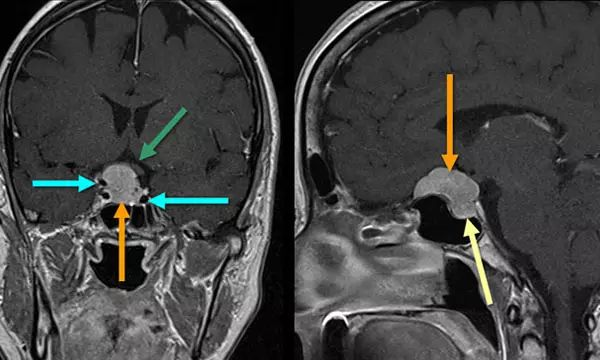

颅底脑膜瘤另一种常见的位置是鞍区。这个部位的脑膜瘤应与其他典型的鞍区肿瘤相鉴别,特别是垂体腺瘤。矢状位MRI扫描(右)表明,肿瘤的基底部位于鞍结节,这是鉴别这种病变与脑膜瘤的一个重要特征。冠状(左)和矢状图像中,橙色箭头指向肿瘤,使视交叉(绿色箭头)位置移动,并包围颈动脉。颈内动脉的流动空隙用蓝色箭头标注。将这种肿瘤诊断为脑膜瘤而不是垂体腺瘤的另一个因素是,垂体表现(矢状图像黄色箭头)与肿瘤截然不同。虽然传统治疗脑膜瘤和垂体腺瘤的手术方法常常涉及开颅手术,但现在这些病变可以通过鼻内镜途径进行,可使脑受到的牵拉减轻。

术后MRI扫描示脑垂体清晰可见(黄色箭头)(与上图为同一患者),肿瘤已行大范围全切除。